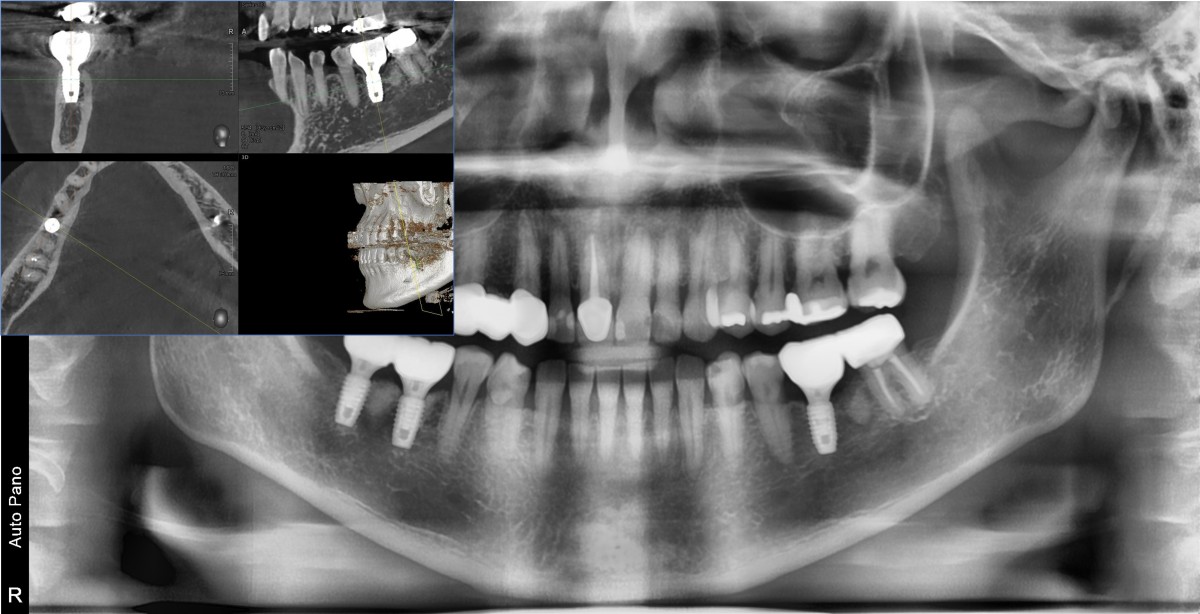

Immediate placement of an implant (Arum Dnetistry NB1, 5*8.5)

A 51-year-old patient complained of an

old-crowned molar. The lower left molar had a gold crown, and the margin showed discoloration indicative of inner caries. Also, it had furcation-involved periodontitis

with an apical lesion.

Extraction and immediate placement of an implant.

▲Arum Dentistry NB1 fixture (5*8.5mm)